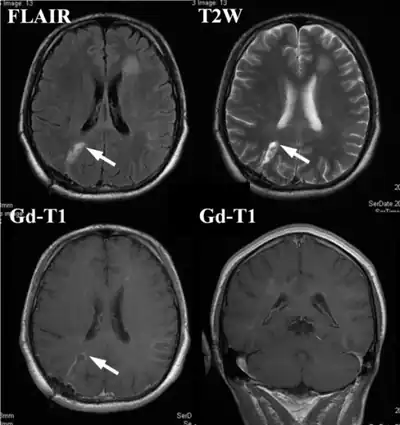

| An example of a ring-enhancement around a lesion in gliobastoma. In tumefactive multiple sclerosis, the ring-enhancement is open, not forming a complete ring. | |

These atypical lesion characteristics include a large intracranial lesion of size greater than 2.0 cm with a mass effect, edema and an open ring enhancement. A mass effect is the effect of a mass on its surroundings, for example, exerting pressure on the surrounding brain matter. Edema is the build-up of fluid within the brain tissue. Usually, the ring enhancement is directed toward the cortical surface.[2] The tumefactive lesion may mimic a malignant glioma or cerebral abscess causing complications during the diagnosis of tumefactive MS. T2-hypointense rim and incomplete ring enhancement of the lesions on post-gadolinium T1- weighted imaging on brain MRI enable accurate diagnosis of TDL[3]

Diagnosis of tumefactive MS is commonly carried out using magnetic resonance imaging (MRI) and proton MR spectroscopy (H-MRS). Diagnosis is difficult as tumefactive MS may mimic the clinical and MRI characteristics of a glioma or a cerebral abscess. However, as compared to tumors and abscesses, tumefactive lesions have an open-ring enhancement as opposed to a complete ring enhancement.[1] Even with this information, multiple imaging technologies have to be used together with biochemical tests for accurate diagnosis of tumefactive MS.[36]

MRI diagnosis is based on lesions that are disseminated in time and space, meaning that there are multiple episodes and consisting of more than one area.[39] There are two kinds of MRI used in the diagnosis of tumefactive MS, T1-weighted imaging and T2-weighted imaging. Using T1-weighted imaging, the lesions are displayed with low signal intensity, meaning that the lesions appear darker than the rest of the brain. Using T2-weighted imaging, the lesions appear with high signal intensity, meaning that the lesions appear white and brighter than the rest of the brain. When T1-weighted imaging is contrast-enhanced through the addition of gadolinium, the open ring enhancement can be viewed as a white ring around the lesion.[40] A more specific MRI, Fluid attenuation inversion recovery (FLAIR) MRI show the signal intensity of the brain. Subjects with tumefactive multiple sclerosis may see a reduction of diffusion of the white matter in the affected area of the brain.[11]